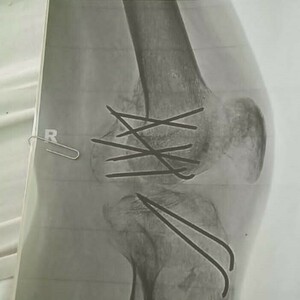

У него диагностировали разрыв тонкого кишечника, перелом 11 ребер, перелом правой ноги, серьезную травму левой. Он до сих пор хромает и ходит с тростью, правая нога до конца не сгибается. Почти год после аварии мужчина носил аппарат Илизарова на правой ноге, ему делали реконструкцию пяточной кости на левой стопе, стягивали пластиной кости после переломе левого запястья. В дальнейшем ему предстоит операция по замене коленного сустава и, возможно, еще одна операция по реконструкции левой стопы. До аварии он подрабатывал тренером в спортзале, теперь – инвалид третьей группы.